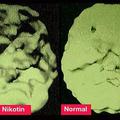

Primerjava Kajenje iz možganov naredi 'švicarski sir' Ameriški nevrolog Daniel G. Amen je predstavil šokantno primerjavo možganov človeka, ki kadi in pije kavo, z zdravimi m…